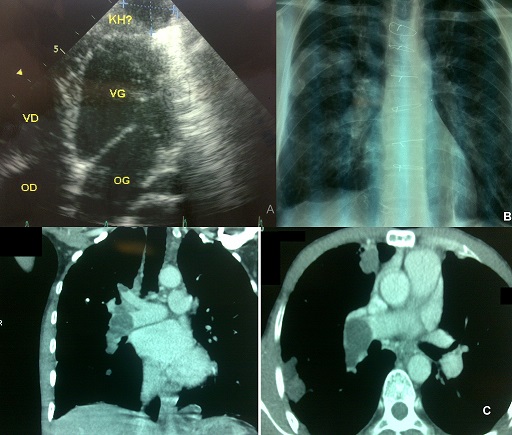

Nous rapportons le cas d'un patient âgé de 39 ans d'origine rurale ayant des antécédents du kyste hydatique du foie en 1995 et d'une hydatidose pulmonaire et péricardique en 2005 traité chirurgicalement et par les antiparasitaires (A). Accusant depuis 15 jours des hémoptysies de moyenne abondance et une dyspnée d'effort. L'examen clinique trouve des râles crépitant et des cicatrices de la sternotomie et de la laparotomie. La radiographie thoracique montre une opacité hilaire droite ronde, de multiples opacités polycycliques axillaires droites et des opacités réticulaires diffuses (B). La tomodensitométrie retrouve une embolie massive par un matériel hypodense kystique intéressant la partie terminale du tronc de l'artère pulmonaire droite s'étendant sur ses branches du lobe inférieur et sur ses branches du lobe supérieur, de multiples kystes hydatiques du lobe moyen et du lobe inférieur droit et un aspect de fibrose pulmonaire bilatérale (C). L'échographie cardiaque et abdominale ne montre pas de récidive. Le bilan fonctionnel montre des troubles ventilatoires restrictifs avec une hypoxie modérée. Le patient est mis sous traitement médical antiparasitaire à base d'Albendazole 800 mg/j pendant 6 mois avec amélioration clinique et radiologique. L'embolie pulmonaire hydatique est une complication rare et grave de la maladie hydatique. Elle succède souvent à la localisation hydatique des cavités cardiaques droites ou de la VCI. Le diagnostic est facile à l'imagerie et le pronostic est très réservé.